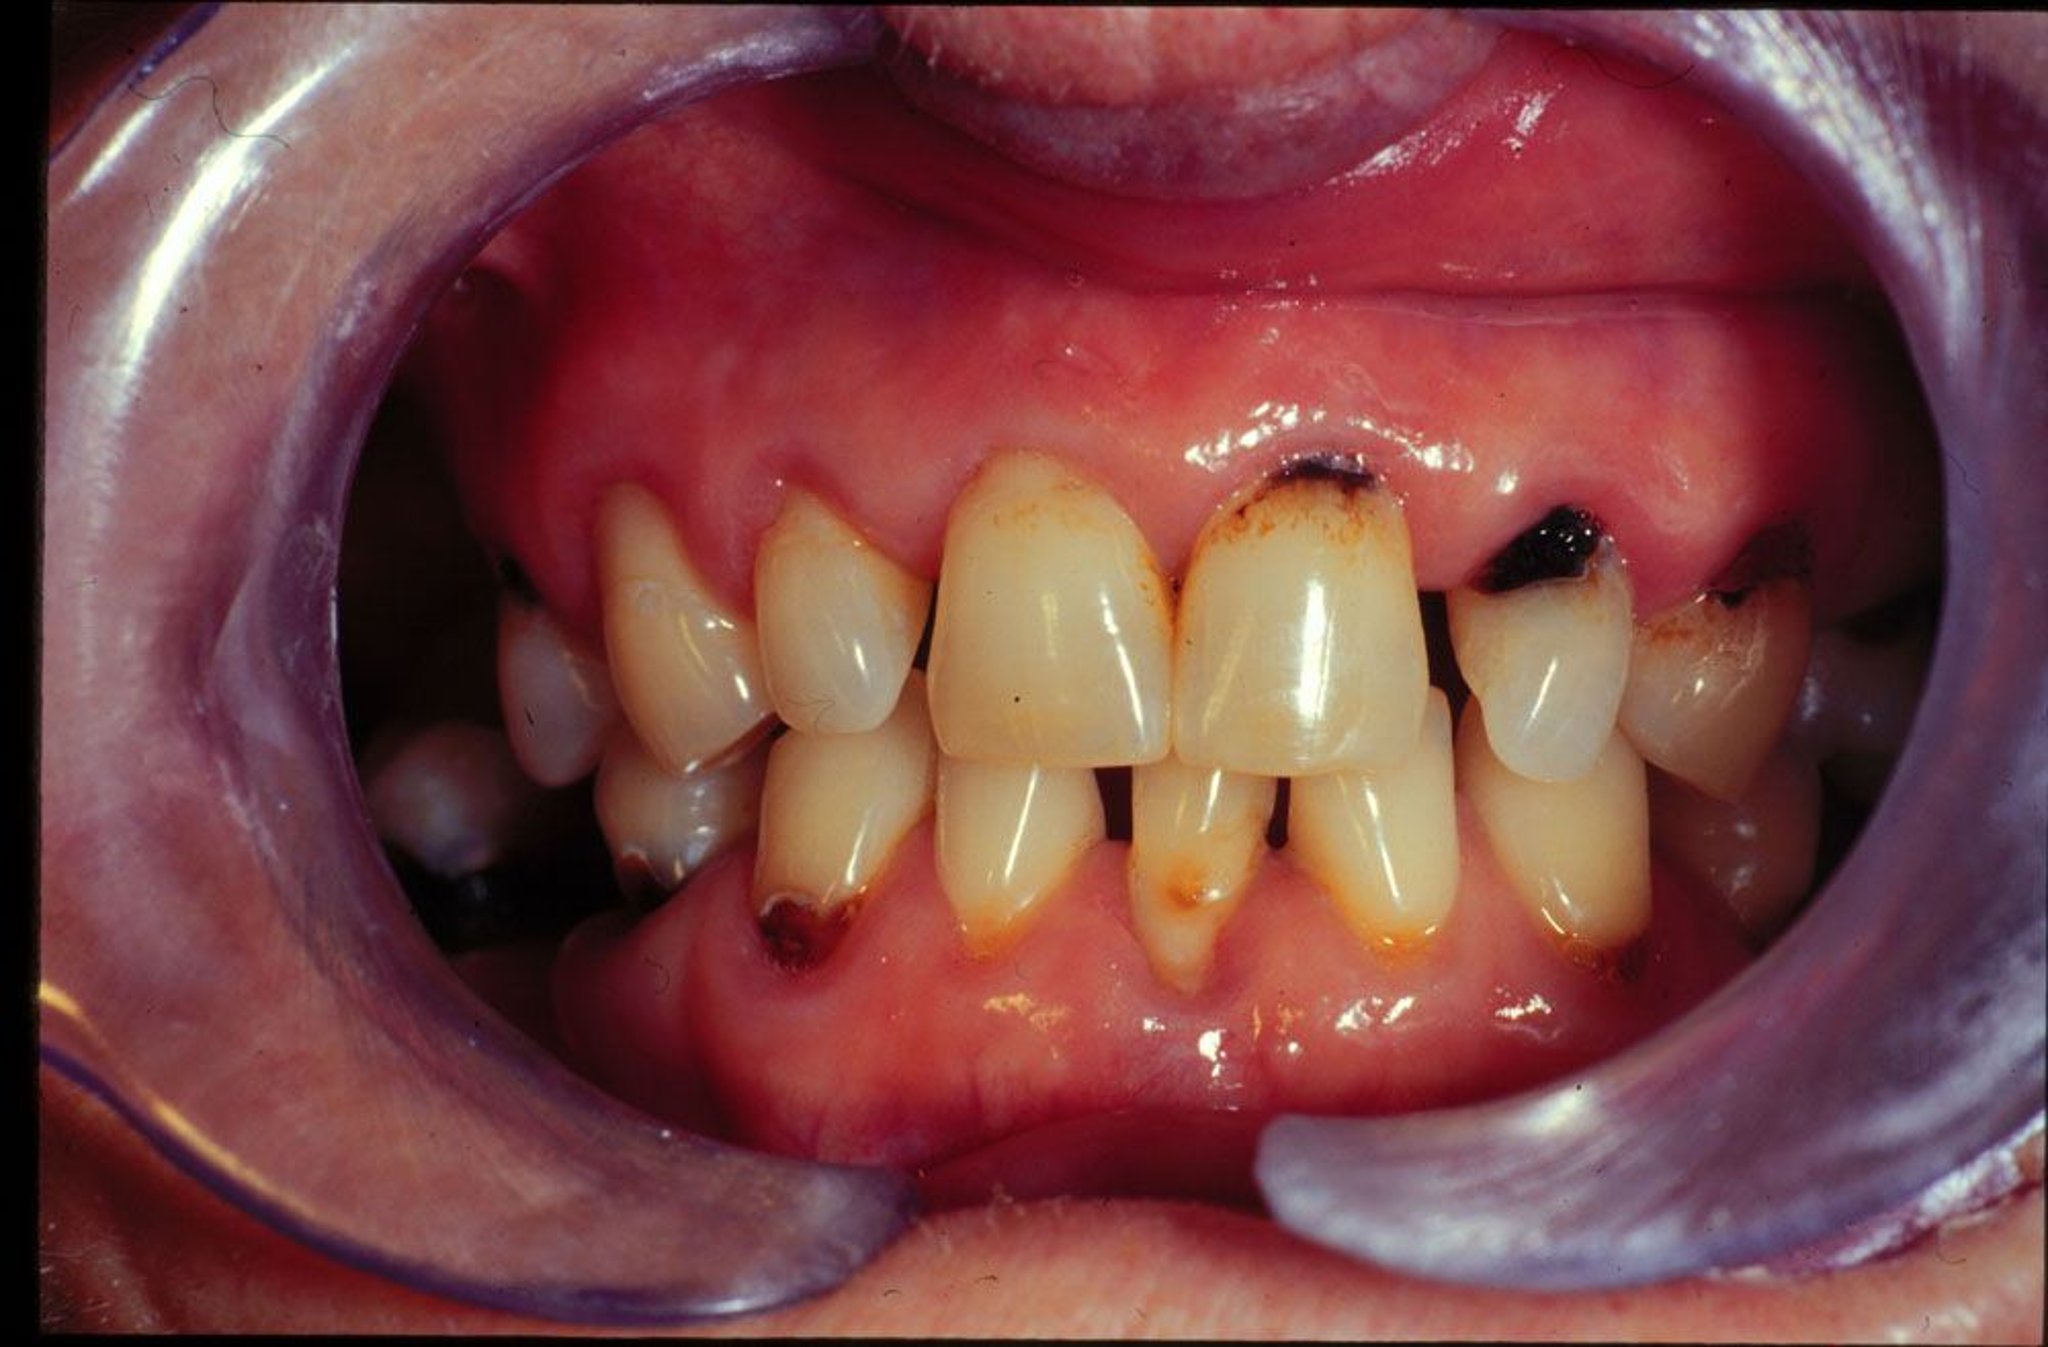

高齢者はしばしば唾液流量を減少させる薬剤を服用し,このことが齲蝕の素因となる。また,高齢者は歯肉の退縮と歯根面の露出,および手の運動能力低下(これにより良好な口腔衛生を維持できない)のため,根面齲蝕の発生率が高い。

齲蝕の症状と徴候

齲蝕は当初エナメル質のみに限局し,無症状である。象牙質に達する齲蝕は,最初は熱い,冷たい,または甘い食べ物や飲み物が歯に触れると痛みが生じ,後には噛んだり叩いたりすると,疼痛を生じる。歯髄への齲蝕浸潤が重度になると(歯髄炎),疼痛は強烈で持続性となる。